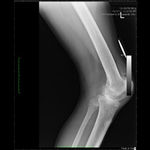

Bilateral Total Knee Replacement was recommended, and performed on July 27th 2011. Since surgery, the patient has made good progress and can now mobilize with the aid of a walker.

His x-rays and clinical examination suggest good early outcome with a fully mobilized patient with pain free knees and the ability to walk independently.

At the present time, he remains under our care and with physiotherapy and self-exercise, he will continue to improve.